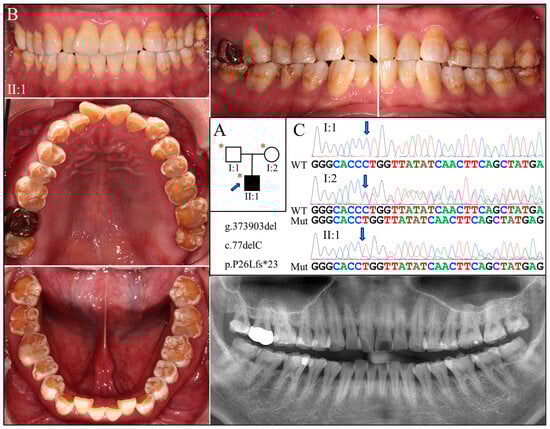

2.3. Families 3 & 4 (c.77del; p.Pro26Leufs*23)